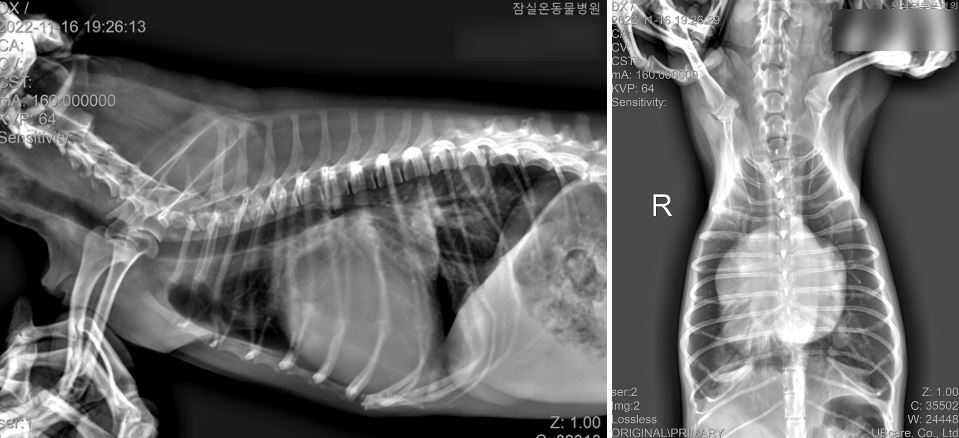

<X-ray 사진 - X-ray상 후폐엽의 미약한 폐침윤 / 좌심 비대 / 우심 비대>

- 실제 방사선상 우심 비대가 확인

- 방사선상에서 폐의 침윤 정도가 미약함